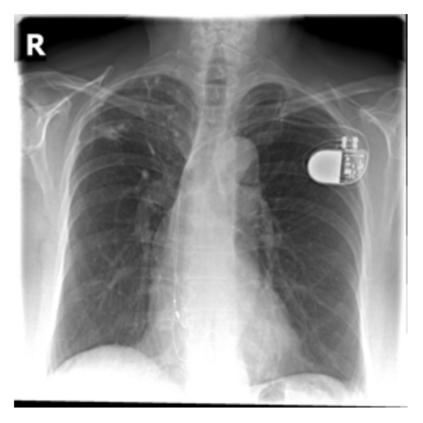

The evaluation of infectious disease processes on radiologic images is an important and challenging task in medical image analysis. Pulmonary infections can often be best imaged and evaluated through computed tomography (CT) scans, which are often not available in low-resource environments and difficult to obtain for critically ill patients. On the other hand, X-ray, a different type of imaging procedure, is inexpensive, often available at the bedside and more widely available, but offers a simpler, two dimensional image. We show that by relying on a model that learns to generate CT images from X-rays synthetically, we can improve the automatic disease classification accuracy and provide clinicians with a different look at the pulmonary disease process. Specifically, we investigate Tuberculosis (TB), a deadly bacterial infectious disease that predominantly affects the lungs, but also other organ systems. We show that relying on synthetically generated CT improves TB identification by 7.50% and distinguishes TB properties up to 12.16% better than the X-ray baseline.